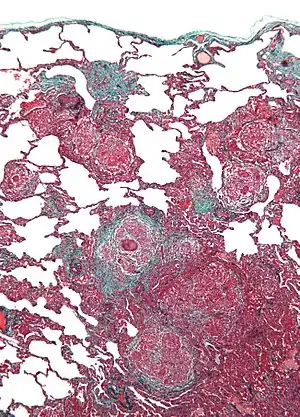

| Micrograph of hypersensitivity pneumonitis, the histologic correlate of bird fancier's lung. Lung biopsy. Trichrome stain. | |

A definitive diagnosis can be difficult without invasive testing, but extensive exposure to birds combined with reduced diffusing capacity are strongly suggestive of this disease. X-ray or CT scans will show physical changes to the lung structure (a ground glass appearance) as the disease progresses. Precise distribution and types of tissue damage differ among similar diseases, as does response to treatment with Prednisone. There are two forms of BFL: acute and chronic. Diffuse alveolar damage (DAD) can occur with acute respiratory failure; progressive interstitial fibrosis is typical of the chronic form.[2] In both, the underlying inflammatory response stops upon exclusion of the allergen,[3] but symptoms may persist depending on the degree of damage already sustained. Among invasive procedures, bronchoalveolar lavage typically shows prominent lymphocytosis with an inverted CD4+/CD8+ ratio, and lung biopsy usually reveals non-necrotizing granulomatous inflammation.[4]